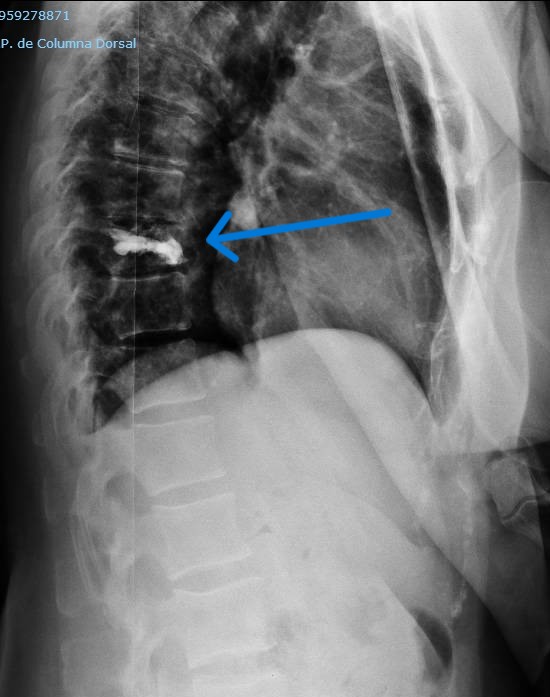

–Fracturas vertebrales: Frecuentes sobre todo en la columna dorso-lumbar, pueden aparecer como consecuencia de mecanismos muy diversos; desde grandes traumatismos, en cuyo caso su tratamiento puede estar condicionado por la presencia de otras lesiones, o bien tras traumatismos banales o incluso de forma espontánea, sin traumatismo alguno. Estos últimos casos definen las «fracturas patológicas» en las que es preciso buscar una causa subyacente estructural o sistémica que haya provocado el debilitamiento óseo. Esta situación es especialmente frecuente en mujeres tras la menopausia debido al desarrollo de osteoporosis. Estos casos precisan iniciar un tratamiento para compensar la desmineralizacón ósea. El tratamiento de las fracturas depende fundamentalmente del grado de deformidad asociado, la afectación de ligamentos (ambos aspectos definen la presencia o no de inestabilidad) y el que exista o no una lesión neurológica. En caso de fracturas estables sin déficit neurológico se emplea una ortesis mientras que en presencia de inestabilidad o afectación neurológica debe valorarse la cirugía.

En el centro y a la derecha se aprecia el TAC postoperatorio en el se ha llevado a cabo la reducción de la luxación con un adecuado alineamiento y fijación combinada anterior mediante caja intersomática y placa así como posterior con tornillos a masas laterales.